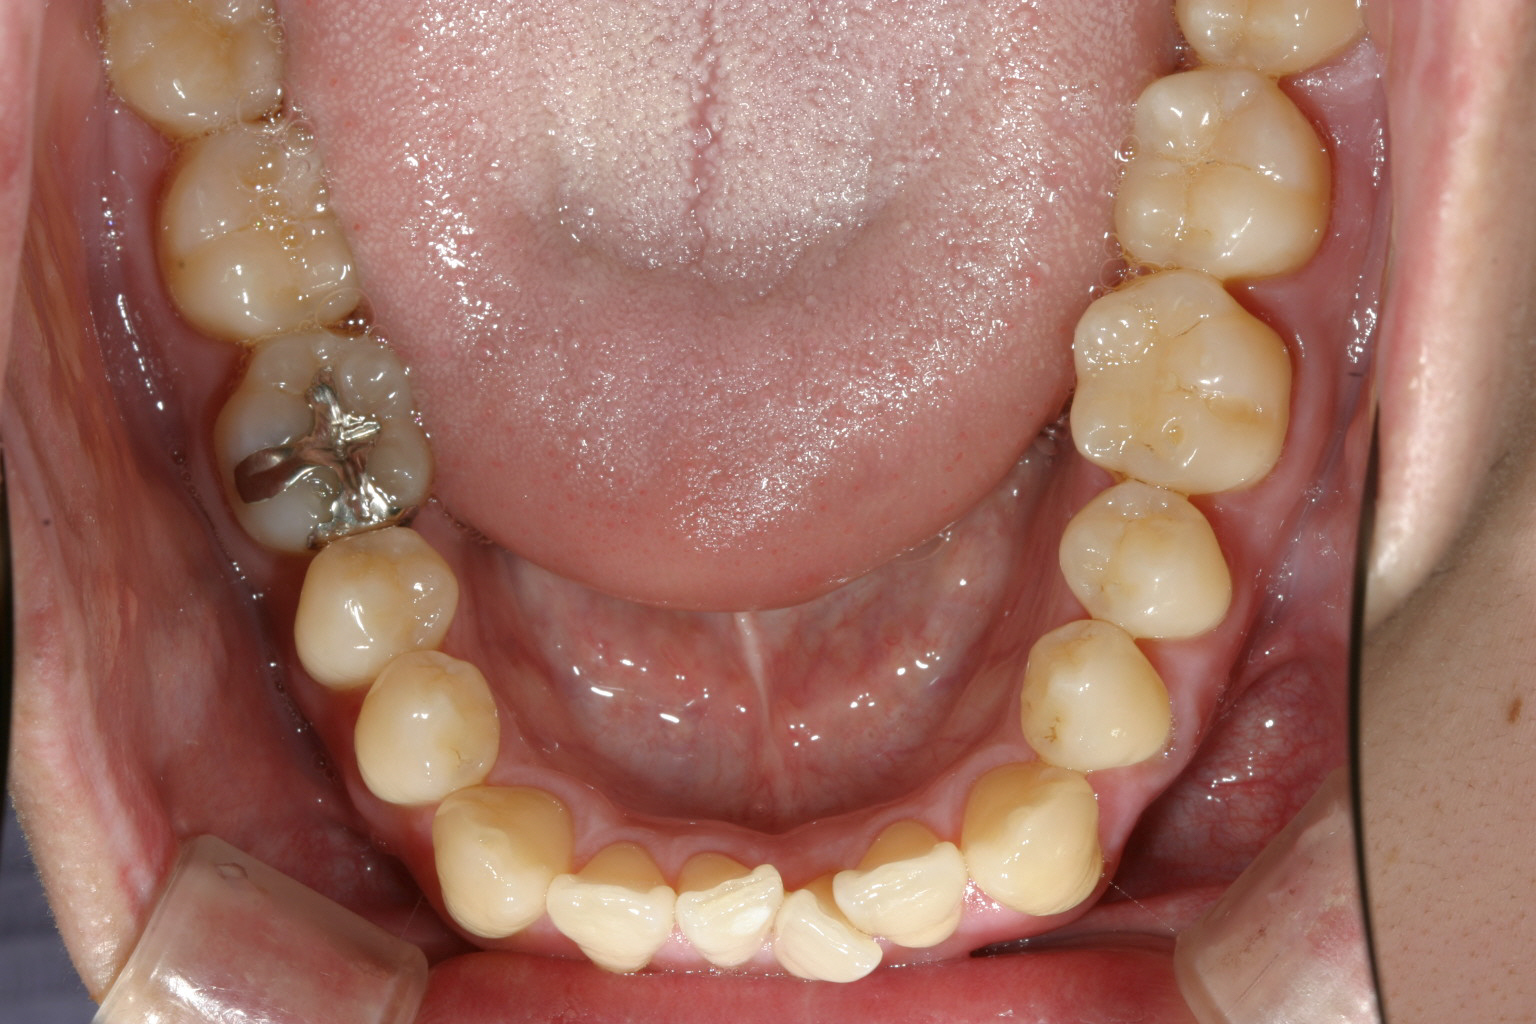

11か月後です。 綺麗なアーチに改善しました。

下顎のアーチも広がり綺麗になりました。

今回のケースはマルチループワイヤーを装着しての矯正となります。

見かけは悪く、違和感も大きいですがメリットはガタガタしていても最初からワイヤ~がブラケットに結紮出来る為、一度結紮できれば24時間仕事してくれるため時間をかなり短縮できる事にあります。

今回のケースも通常は2年前後かかるケースですが、僅か11ヵ月でワイヤーを外す事が出来ました。